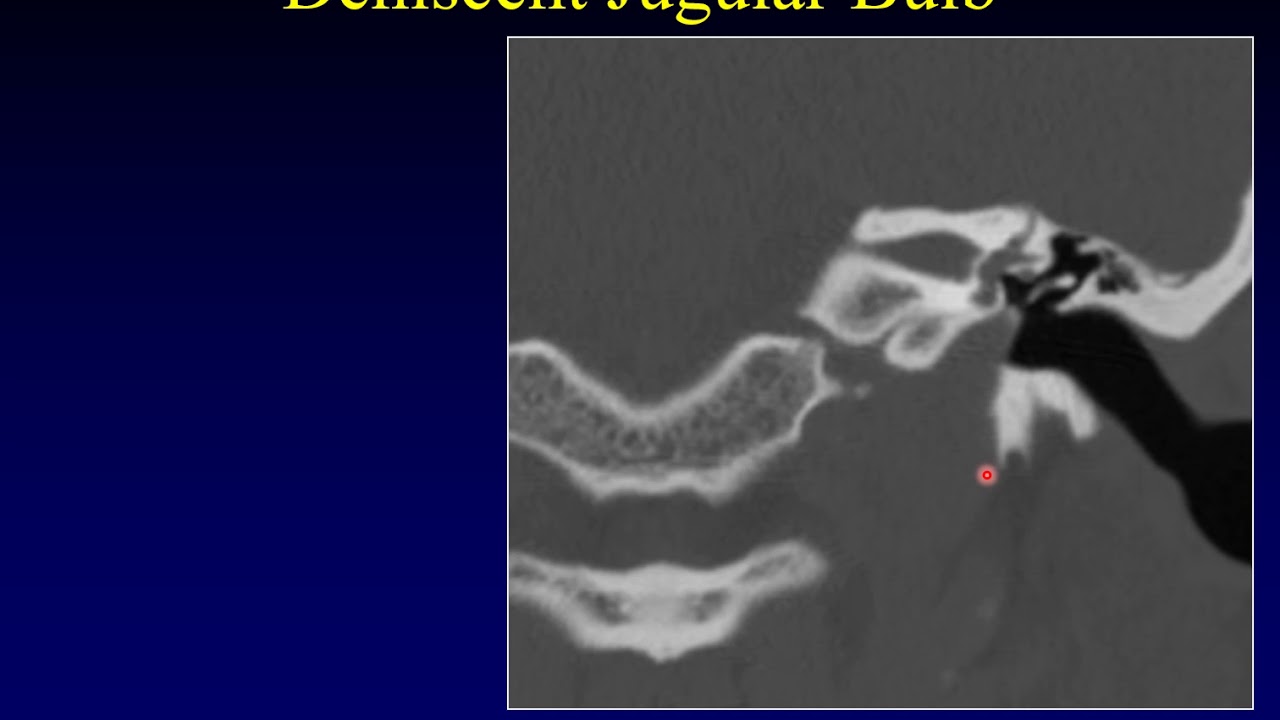

Axial Anatomy of EAC - MRI Online скачать в хорошем качестве

Axial Anatomy of EAC - MRI Online

MRI Mastery Series: External Auditory Canal (EAC) presented by Dr. David Yousem https://mrionline.com/courses/mri-mas... The external auditory canal can be thought of as a vestibule to the temporal bone. Most people have a lot of fear about the anatomy of the temporal bone. But when broken down into external auditory canal, middle ear, and inner ear, the EAC is probably the easiest area and a great place to start learning about temporal bone pathology. Within the temporal bone, and within the external auditory canal, there are many potential causes of conductive hearing loss. This course will describe for you several of the lesions that are associated with external auditory pathology both on the congenital basis, as well as on the non-congenital basis, which includes great infections, great potential neoplasms, and other pathologies that are worth understanding. Subscribe to our channel and hit the notification bell so you can be alerted when we upload a new video: ► https://www.youtube.com/MRIOnline?sub... An MRI Online membership gives you unlimited access to our course library full of scrollable DICOM images and micro-learning video courses. ► https://mrionline.com/courses/ Try MRI Online free for 7-days with unlimited course access.► https://mrionline.com/mri-online-prem... MRI Online partners with proven educators to create the best training experiences for radiologists in every stage of their career. Get exposure to 1000’s of cases and become a more accurate, confident and efficient reader.► https://mrionline.com/mri-online-prem... Our library of courses is a great complement to a residency's core training curriculum; learn how MRI Online can bolster your training program and help with ACGME compliance. Compliment your program's curriculum with MRI Online: https://mrionline.com/resident-member... What do students say about MRI Online? “I really enjoy this teaching format over the standard lecture. Looking at cases cold is so much more effective than watching someone show you pictures for hours. I love it.” - Dr. Derek Archer - Toronto, Canada “I believe you are a revolutionary organization that is positively disrupting the way we train future MRI radiologists. Well done.” - Dr. Rocki Doss - Perth, Australia Be sure to subscribe for more interesting MRI vignettes like this one: https://www.youtube.com/MRIOnline?sub... FOLLOW US: Twitter ►   / themrionline   Facebook ►   / themrionline   Linkedin ►   / 19038247   Youtube ► https://www.youtube.com/MRIOnline?sub...